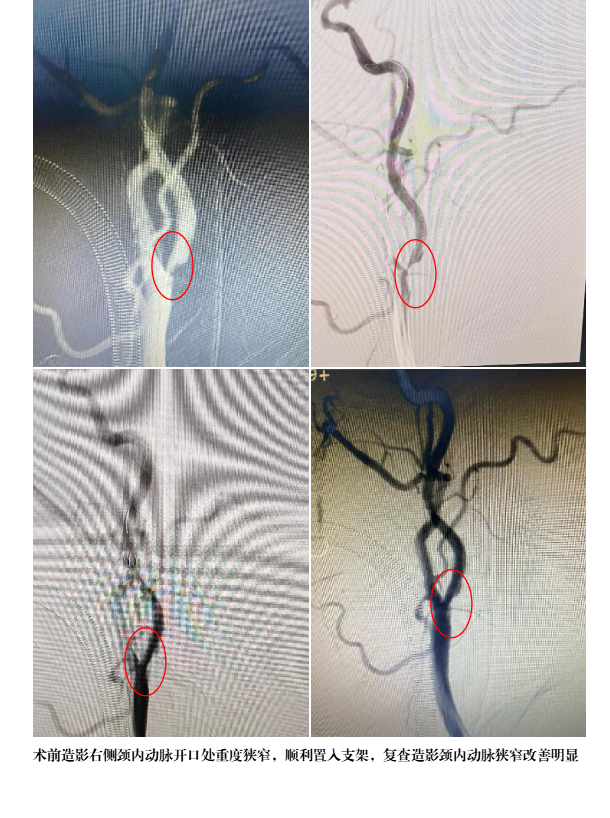

患者男性,66岁,近年来反复出现头晕、头痛,与近日就诊于原州区人民医院神经外科,CTA及彩超检查后发现右侧颈内动脉重度狭窄,狭窄程度达81%。神经外科主任万欣龙立即组织医疗团队,(福建医科大学附属第一医院“组团式”帮扶专家周志伟、神经外科团队、手术麻醉科)开展病例评估及讨论治疗方案,因患者既往行下颌骨肉瘤切除并且长期放化疗,行颈动脉剥脱术存在风险,经反复与患者及家属充分沟通后,在全麻下行“全脑动脉造影+经皮右侧颈内动脉球囊扩张+支架置入术”,术程顺利,造影颅内血管未见明显异常,术后患者无任何不适。

2.支架植入术是一种治疗颈内动脉狭窄的方法,它通常与颈内动脉血管成形术联合使用。在这个过程中,医生会通过经皮穿刺股动脉(或者桡动脉)完成治疗通道的建立,然后将保护伞送达颈内动脉远端(保护治疗期间斑块脱落),接着送入球囊预扩张狭窄处,最后将支架植入支撑颈内动脉狭窄处,完成整个手术过程。